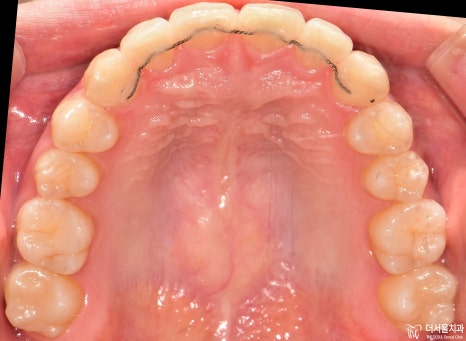

먼저 교합면에서 보게 되면, 앞니들의 총생이 관찰됩니다.

그래서 인비절라인 클린첵 시뮬레이션으로 확인을 해야 됩니다.

인비절라인 클린첵 시뮬레이션 진행

치열이 변화가 되는것을 한 눈에 볼 수 있죠? 이게 인비절라인의 장점입니다.

다행히 비발치교정 으로 진행이 가능하다는 판단이 나왔으며 어금니들의 위치 이동에 따라서

일부 공간을 확보하면서 앞니들을 뒤로 넣는 치료 계획이 수립되었습니다.

치아의 표면에 인비절라인의 치아 이동 핵심 원리인 어태치먼트들이 붙여져 있습니다.

뾰족뾰족 튀어나온 것들이, 투명 템플릿과 서로 맞물려서 상호작용을 일으키는거고

이 힘 때문에 앞서 보여드렸은 클린첵 시뮬레이션 결과를 그대로 환자께 드릴 수 있는겁니다.